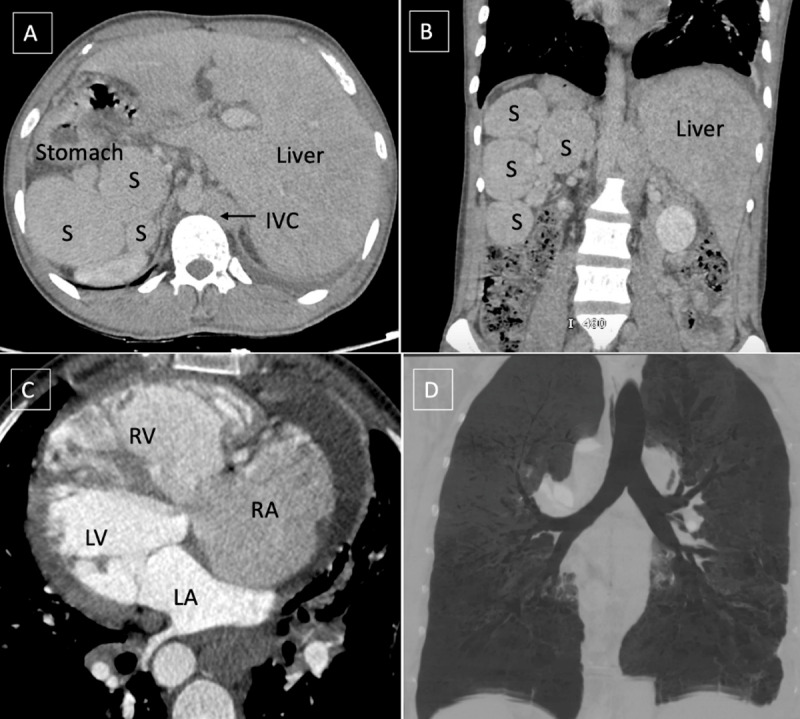

Incidental detection of polysplenia associated with situs inversus totalis in an adult is rarely reported in literature.12 "Heterotaxy" refers to a wide spectrum of anomalies involving dysmorphism of thoracoabdominal organs across the right-left axis of the body. Polysplenia is observed in left isomerism along with bilateral bilobed bronchi and bilateral morphologic left atria. However, in this case, polysplenia was present without isomerism.